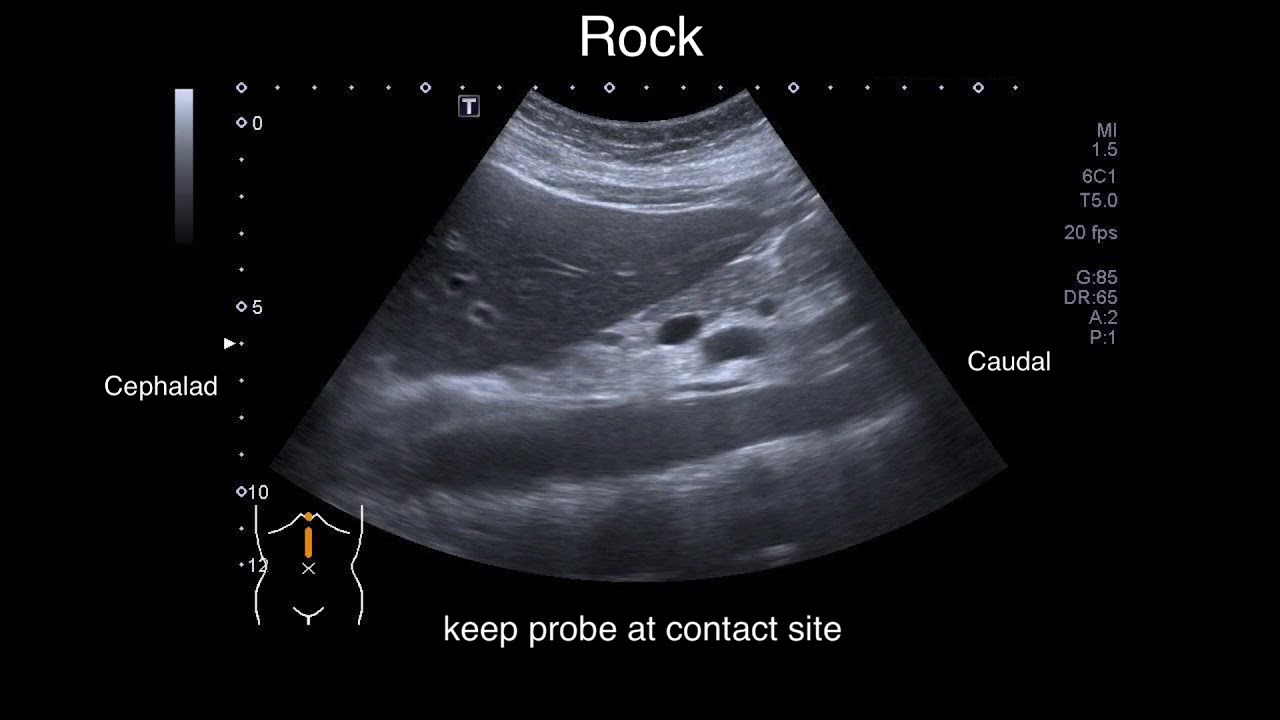

복부 초음파 검사는 내부 장기 상태를 실시간으로 확인할 수 있는 비침습적이고 안전한 검사 방법입니다. 많은 사람들이 건강검진이나 특정 증상이 있을 때 이 검사를 받는데, 이를 통해 다양한 질환이나 건강 상태를 확인할 수 있습니다. 특히, 복부 초음파는 간, 신장, 췌장, 담낭 등을 포함한 여러 장기의 상태를 검사할 수 있는 중요한 도구로 활용됩니다.

복부 초음파 검사는 환자에게 특별한 준비가 필요하지 않은 간단한 검사입니다. 보통 20분에서 30분 정도 소요되며, 검사 전에는 식사를 금지하거나 적당한 시간 동안 공복 상태를 유지해야 하는 경우가 많습니다. 초음파 검사에서는 젤을 피부에 바르고, 초음파 기기를 복부에 대고 화면을 통해 내부 장기를 확인합니다. 환자는 검사 동안 편안한 자세를 유지해야 하며, 검사 후에는 특별한 후유증이나 회복 시간이 필요하지 않습니다.